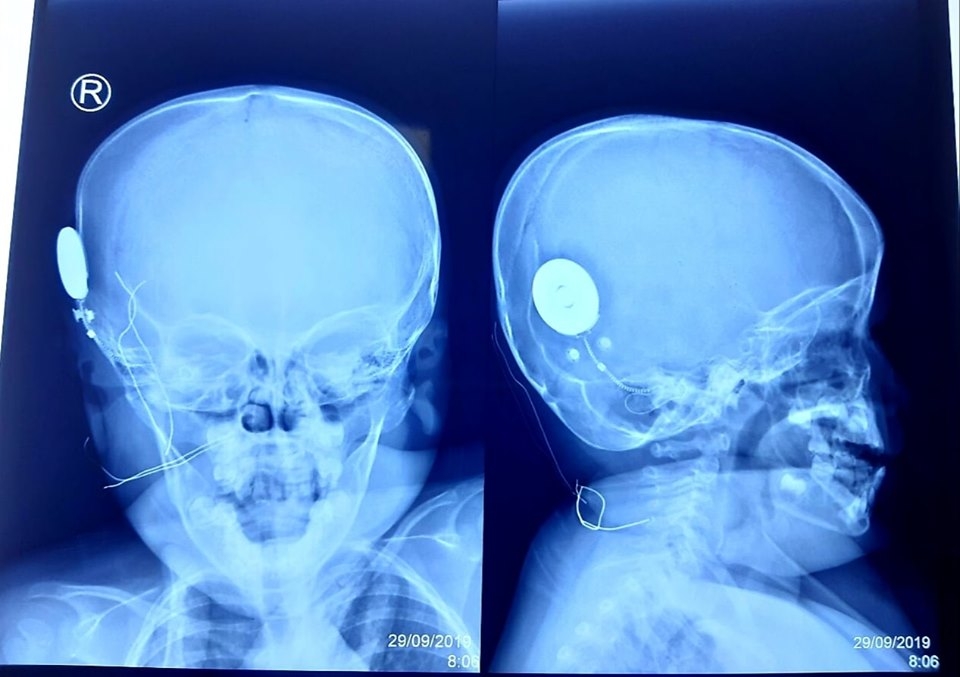

Để thực hiện ca cấy điện cực ốc tai đầu tiên này, các bác sĩ Tai Mũi Họng cùng đội ngũ Gây mê Hồi sức đã chuẩn bị một cách chu đáo mọi mặt. Ca phẫu thuật được thực hiện trong 2 giờ với sự tập trung của toàn thể ekip các bác sĩ. Sau khi đặt điện cực ốc tai, các chỉ số kiểm tra hoạt động của tất cả các điện cực bằng cách đo trở kháng và trường (Impedence and Field Telemetry IFT) và đo đáp ứng thần kinh hạch xoắn ốc tai ART (Audio nerver Respond Telemetry) đều rất tốt. Ca phẫu thuật thành công đã mở ra một bước ngoặc mới trong cuộc đời của bệnh nhi.

| Ca phẫu thuật thành công, mang lại thính giác cho bệnh nhi |

Theo BS.CK2 Bạch Thiên Phương - Trưởng khoa Tai Mũi Họng Bệnh viện Nhi đồng Thành phố - Trưởng ekip cấy điện cực ốc tai cho bệnh nhi, cấy ốc tai điện tử là phẫu thuật cấy ghép hệ thống điện tử phức tạp vào tai trong để kích thích dây thần kinh thính giác chuyển các xung động thần kinh lên não khiến người điếc nghe được âm thanh. Trẻ được cấy điện cực ốc tai càng sớm thì sự phát triển ngôn ngữ càng cao, tốt nhất là trước 2 tuổi. Trẻ không thể nghe nói bình thường ngay sau khi được cấy ốc tai mà cần phải có quá trình làm quen với âm thanh, tập nghe nói lâu dài để có vốn từ, tham gia các khóa huấn luyện ngôn ngữ với chuyên gia thính học. Ngoài ra, sự hợp tác kiên nhẫn của gia đình cũng rất quan trọng trong việc giúp cho trẻ phát âm, phát triển ngôn ngữ, giao tiếp với môi trường xung quanh.